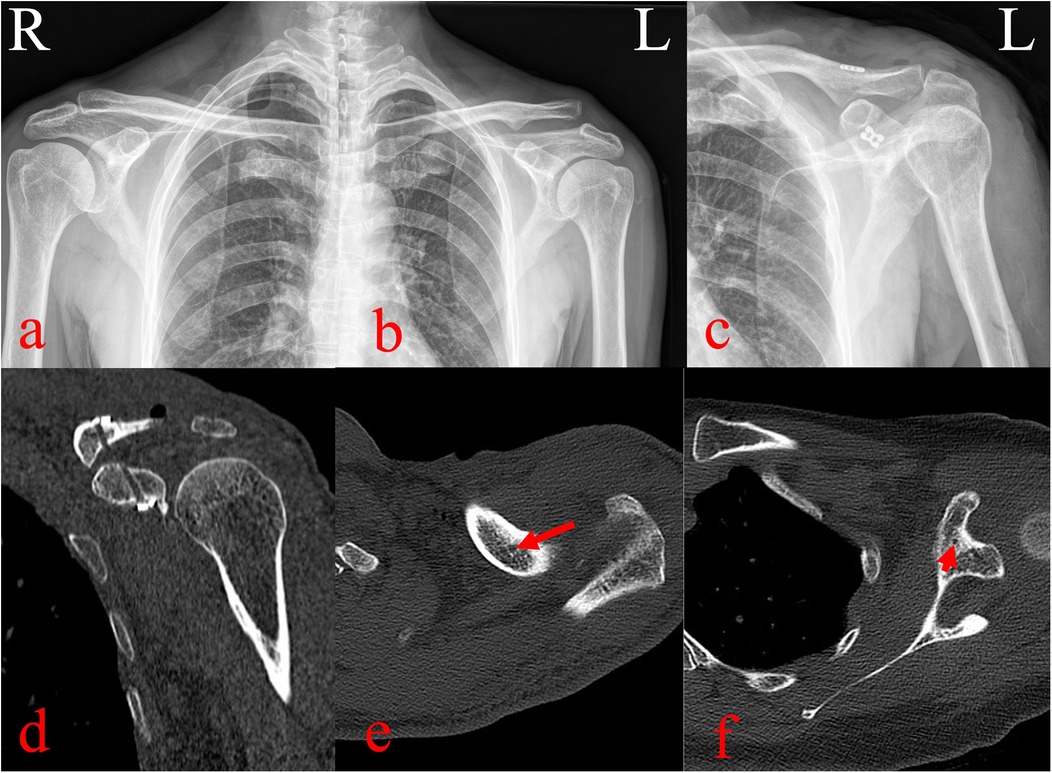

The AC joint was manually reduced, and the loop was tensioned and tied. C-arm fluoroscopy confirmed complete reduction of the AC joint. The x-rays and three-dimensional computed tomography was taken the day after surgery (Figure 3). The incisions were disinfected and closed in layers. Postoperatively, the oral loxoprofen (60 mg) were administered three times daily for three days. Rehabilitation included passive motion from day one, brace immobilization for four weeks, initiation of active exercises at six weeks, and return to normal activities at three months. Follow-up visits were conducted with x-rays at 3, 6 and 12 months postoperatively, during which the shoulder joint functional recovery and visual analog scale (VAS) were meticulously documented.

Figure 3

X-ray and CT images of a shoulder. Panels a and b show an X-ray from the front and side view of the left shoulder. Panel c shows an X-ray from a lateral view, indicating displacement. Panels d, e, and f are CT scans highlighting the os acromiale, with red arrows pointing to areas of interest.

Figure 3. Pre- and postoperative imaging evaluation. (a–b) Preoperative radiographs showing >100% displacement of the left AC joint. (c) Postoperative radiographs showing anatomic reduction with appropriate placement of the ALP and four-leaf clover plate. (d–f) Three-dimensional computed tomography reconstructions confirming central positioning of clavicular and coracoid bone tunnels with satisfactory implant placement.

Pain decreased from a VAS score of 6 preoperatively to 2 on day three, and to 0 at three months. At one year, the Constant-Murley score was 98. Tunnel enlargement was observed at 3 months, progressed slightly by 6 months, and stabilized thereafter without clinical consequence. At the 1-year follow-up, the clavicle tunnel showed no further widening compared with the 6-month findings. A minor loss of acromioclavicular joint reduction was noted, and the patient remained asymptomatic with good functional recovery (Figure 4). The Constant-Murley score reached 98, and serial radiographs confirmed reduction of the AC joint without redislocation or complications such as clavicular or coracoid fractures.